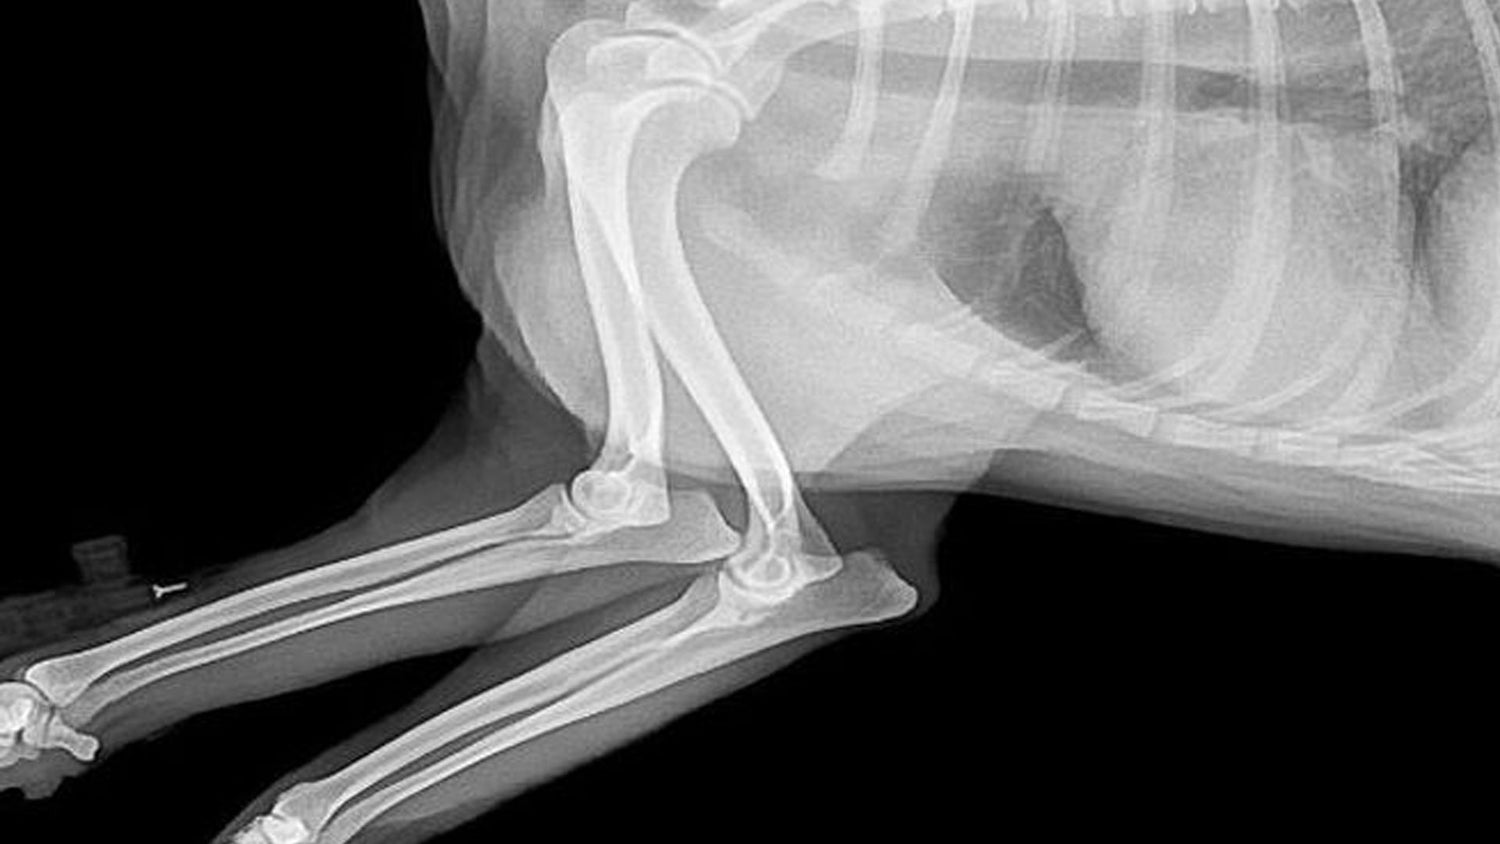

Radiología

Contamos con tecnología de radiografía digital para obtener diagnósticos precisos y rápidos. Este servicio nos permite evaluar huesos, órganos y tejidos internos de tu mascota sin procedimientos invasivos, ayudándonos a detectar fracturas, enfermedades y otros problemas de salud de manera eficaz.